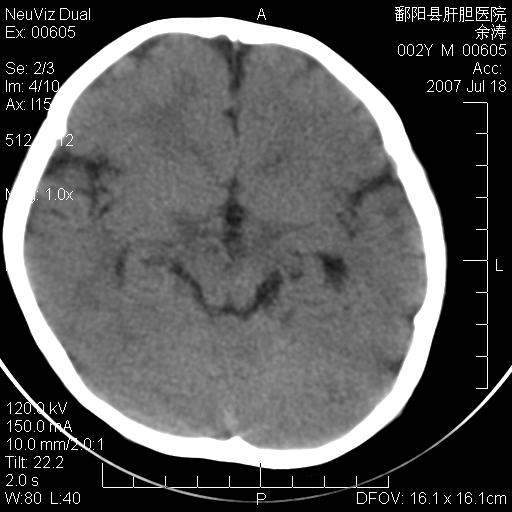

男性 2岁:平时智力障碍。外伤后行颅脑平扫。

3\\透明隔间腔

脑裂畸形;左侧脑脑萎缩;透明隔囊肿;血管畸形?